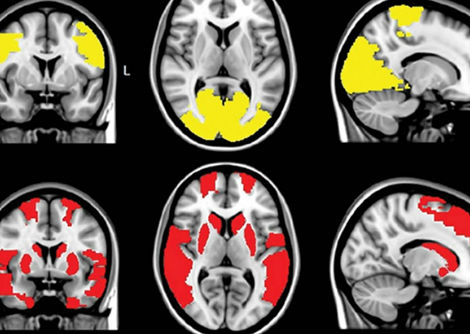

أما عن سبب ظهور هذه العلاقة فإننا نعرف أن الجسم يتفاعل بشكل طبيعي مع البرد، حيث يبدأ القلب بالنبض بشكل أسرع للحفاظ على الدفء كبداية، كما يشد الجسم الشرايين استجابة للبرد مما يقلل من التوصيل الحراري في الجلد و رفع ضغط الدم نتيجة لذلك.

التغيرات الهرمونية التي تحدث استجابة للبرد تجعل الدم أكثر عرضة للتجلط. يمكن لأي من هذه التغيرات البيولوجية أن تسبب مشاكل في القلب والأوعية الدموية عند انخفاض درجة الحرارة عن طريق جعل الظروف الحالية أسوأ.